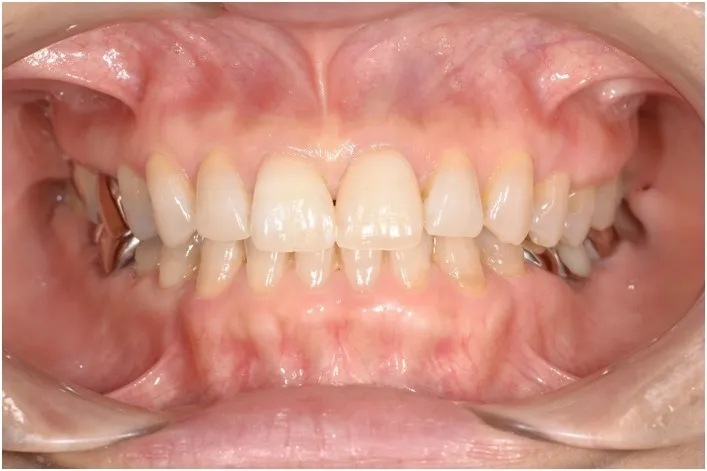

美しいスマイルライン ~ラミネートベニア~

白くしたい歯がさし歯などの場合は、セラミッククラウンに入れ替えることで白く自然な歯にすることができますが、天然の歯の場合、できるだけ健全な歯質は削りたくありません。そんな場合にはラミネートべニアという治療法を用いることで、理想のスマイルラインに近づける事も可能です。歯並びは口元の印象を大きく左右するポイントの1つで、自然な弧を描く口元はいい印象を与えます。

【治療後】

【治療期間】2週間~1か月

【メリット】天然の歯と同じような光を通すため、自然な歯の仕上がりになります。歯をほとんど削りません。長くきれいな色調を維持できます。

【デメリット】強度は高いですが、噛み合わせの悪い人や歯ぎしりがひどい場合はラミネートべニアが割れる場合もあります。

【費用】¥120,000〜150,000(税抜)